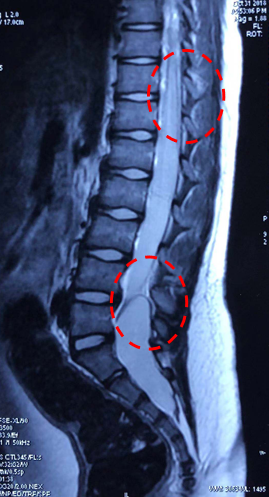

男,8岁大小便失禁伴双下肢肌力下降25天小便失禁为突出症状诊断:骶管囊肿、脊髓圆锥中央管扩张?表皮样囊肿?

缝合硬膜术后小便症状明显改善

术后小便症状显著改善

本例脊髓圆锥及终丝呈囊性扩张,术中探查未见表皮样囊肿成分